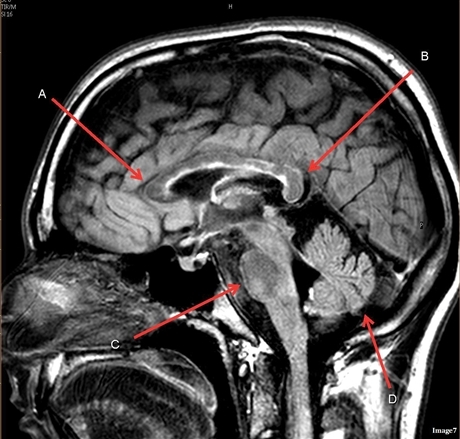

Image weighting and axis

T1 Sagittal

A

Lateral Ventricle

B

Corpus Callosum

C

Thalamus

D

Tentorium

E

4th Ventricle

F

Medulla Oblongata

Genu Corpus Callosum

Splenium Corpus Callosum

Pons

Cerebellum